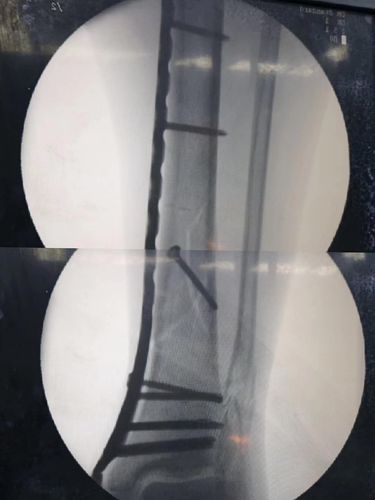

骨折接骨,跖骨骨折

手术演示:盖氏骨折微创钢板接骨术

微创接骨板接骨术(mipo)在胫腓骨远端骨折中的应用

接骨手术